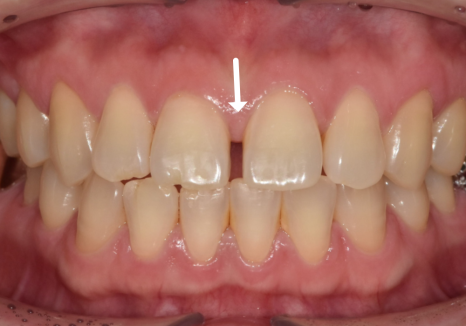

얼마 전 저희 치과를 찾으신 환자분은

가운데 앞니가 벌어진 상태였고,

동시에 왼쪽 위 어금니(#26)도

상실된 상태였어요.

라미네이트를 통해

앞니 4개의 균형을 맞추고 나니,

단 며칠 만에 인상이 훨씬 단정해지셨습니다.